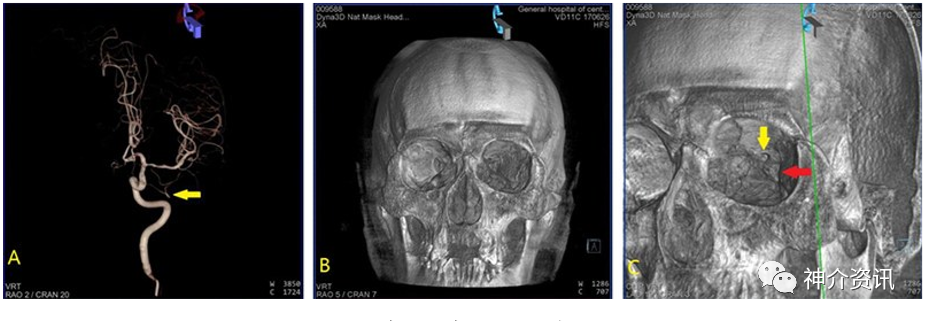

收集100例DSA检查无异常发现的病人,利用其三维脑血管成像及三维颅骨成像数据,在Siemens双C臂机Syngo后处理工作站,进行三维数据融合,获得3D-DSA/3D-CT的融合影像,选择颅眶区手术入路的步骤,对血管影像与颅骨相关及毗邻关系进行观察并测量与手术入路相关的数据,在三维静态(冠状位、矢状位、轴位及与手术相关的角度)与连续动态融合影像模拟手术入路步骤进行操作。

观察发现多数眼动脉起始部位于颈内动脉床突段内侧,沿视神经管外下方走行。颅骨左右径平均(143.89±5.78)mm,颅骨前后径平均(173.14±5.68)mm,双侧眼动脉起始处至视神经管上壁距离平均(7.32±2.42)mm,视神经孔到眶上裂距离平均(2.42±0.69)mm。在三维融合影像中发现2例眼动脉未经视神经管入眶的变异。

颅眶手术入路双容积融合影像,与单一影像相比,可显示手术入路的相互比邻解剖关系,对手术有更精准的参考价值。应用手术对象的融合影像显示手术入路,可达到标准化、个体化,对手术参考价值更大,更符合手术真实情况。